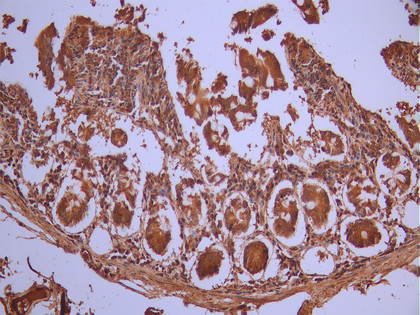

IHC image of CSB-RA091918A0HU diluted at 1:100 and staining in paraffin-embedded human small intestine tissue performed on a Leica BondTM system. After dewaxing and hydration, antigen retrieval was mediated by high pressure in a citrate buffer (pH 6.0). Section was blocked with 10% normal goat serum 30min at RT. Then primary antibody (1% BSA) was incubated at 4°C overnight. The primary is detected by a Goat anti-rabbit polymer IgG labeled by HRP and visualized using 0.05% DAB.

IHC image of CSB-RA091918A0HU diluted at 1:100 and staining in paraffin-embedded human cervical cancer performed on a Leica BondTM system. After dewaxing and hydration, antigen retrieval was mediated by high pressure in a citrate buffer (pH 6.0). Section was blocked with 10% normal goat serum 30min at RT. Then primary antibody (1% BSA) was incubated at 4°C overnight. The primary is detected by a Goat anti-rabbit polymer IgG labeled by HRP and visualized using 0.05% DAB.